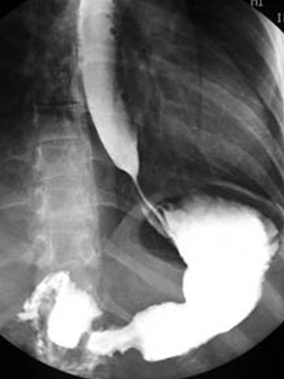

. La TOGD en double de contrast ( baryt + air +

hypotonie medicamentuese ) peut evite la superposition du

duodenum et du grele sur estomac et ce qui augemente

detection detaillee de la muqueuse gastrique et les niches de face de

l'estoma . Cette methode essentiellement utilisee pour estoma et le

colon , et rarement sur l'intestin grele .

| TOGD de estomac normale en

double de contrast |

Ulcere de la petite courbure en double de

contrast |

Images en double de contrast

d'une ulcere du paroi posterieure de estomac . |